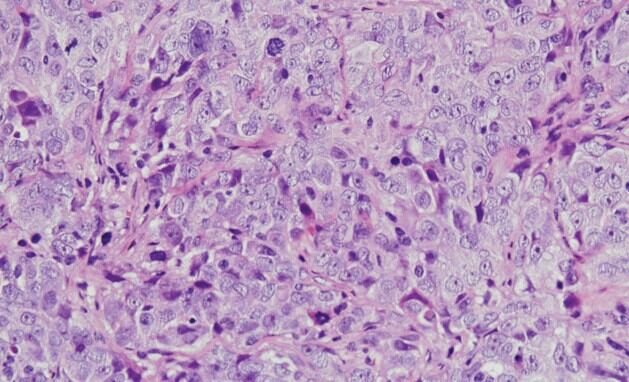

Cáncer de ovario seroso de alto grado CSIC

El cáncer de ovario es uno de los cánceres ginecológicos más mortales en las mujeres. Cada año se diagnostican en todo el mundo unos 300.000 nuevos casos y se producen unas 200.000 muertes. La mayoría de los cánceres de ovario son de origen epitelial y, de ellos, más del 70 por ciento se catalogan como tumores de ovario de alto grado y suelen diagnosticarse en un estadio avanzado, dado que no presentan síntomas ni signos específicos en su fase inicial. Estas circunstancias le confieren un mal pronóstico y exigen el desarrollo de nuevas estrategias terapéuticas para combatir la evolución de la enfermedad.

Esto llevó a la identificación de una proteína, denominada WNK1, que se encontraba anormalmente activa en las líneas celulares analizadas. Este resultado impulsó el análisis del estado de activación de esta proteína en tumores de pacientes diagnosticadas con diferentes tipos de cáncer de ovario en el Hospital Universitario de Salamanca, revelando que la activación anormal de WNK1 afectaba drásticamente a la supervivencia de las pacientes.